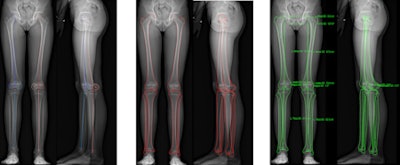

Another method, biplanar low-dose DR with a 2D/3D system (EOS Imaging), uses two orthogonal sources of radiation and linear digital detectors that produce two orthogonal x-ray images of the lower limbs in the standing position. The system generates surface 3D reconstructions and measurements of the lower limbs, and 2D measurements of the lower limbs, automatically generated from 3D reconstructions.

The group took 3D measurements of eight dried bones, analyzing them with the EOS system using stereoscopic software and comparing the measurements with 3D CT. Also, 47 lower limbs of children and adolescents were studied using biplanar low-dose x-ray 2D and 3D measurements. Both parts of the study were evaluated for femoral length, tibial length, femoral mechanical angle, tibial mechanical angle, frontal and lateral knee angulations, and the femoral neck-shaft angle.

Above: From left to right, the calibration points, the contours, and the 3D measurements. Below: From left to right, 3D reconstructions views: frontal, lateral, back, up, and down. All images courtesy of Dr. Ramon Gheno.

The researchers found the 3D comparison between the EOS system and CT showed no significant differences in femoral length, tibial length, femoral mechanical angle, tibial mechanical angle, frontal knee angulation, lateral knee angulation, and femoral neck-shaft angle.

However, 2D and 3D measurements from the EOS system demonstrated significant differences in tibial length, femoral mechanical angle, and femoral neck-shaft angle.